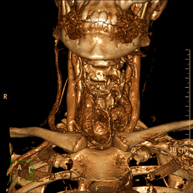

- Angio – TC Troncos Supraaórticos

Prueba radiológica que consiste en obtener imágenes de las arterias carótidas del cuello de alta definición anatómica mediante el empleo de un equipo de TC (Tomografía Computarizada) y la inyección de contraste intravenoso. Posteriormente, las imágenes son reconstruidas en tres dimensiones (3D). Indicaciones: accidente vascular cerebral agudo, accidente vascular transitorio, soplo carotídeo.